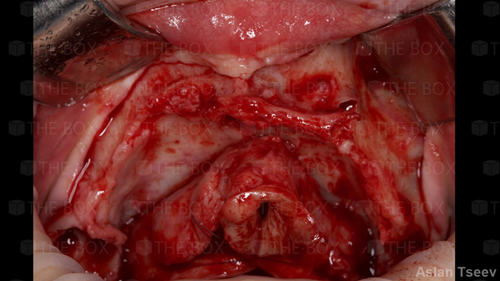

Infra bony defect one wall defect follow up 18 months show regeneration of buccal bone and interdental defect utilizing allograft bone substitute